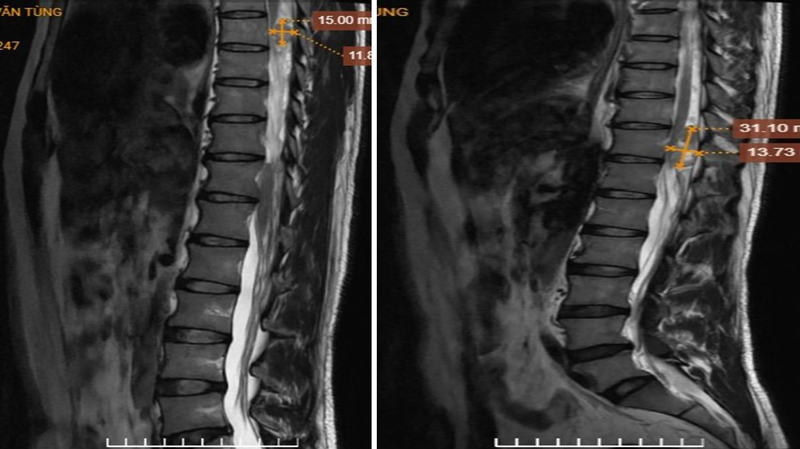

Hình ảnh khối trong ống sống vị trí T7, T11, cạnh phải lỗ tiếp hợp bên phải L1/2 trước và sau tiêm thuốc đối quang từ

Để xác định nguyên nhân, bệnh nhân được chỉ định chụp MRI có tiêm thuốc đối quang từ. Kết quả cho thấy, trên các chuỗi xung khảo sát chi tiết xuất hiện các khối trong ống sống tại mức đốt sống ngực T7, T11 và khối khu trú cạnh lỗ tiếp hợp bên phải mức L1/2. Các đặc điểm hình ảnh hướng đến chẩn đoán u bao dây thần kinh (Schwannoma) đa vị trí trong ống sống.